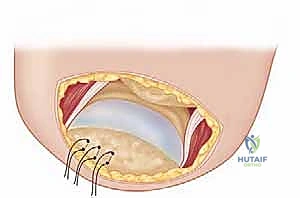

Placement of Suture Anchors:

- Pre-place several suture anchors (typically 3-5, depending on the size of the footprint and tendon) into the prepared greater tuberosity. The number and type of anchors will vary based on surgeon preference. I prefer a double-row technique for robust fixation.

- Surgeon's Directive: "Let's place our anchors now. Aim for strong purchase in good bone. We'll use these to secure our transferred latissimus."

FIG 5 • A. The recipient bed on the greater tuberosity is prepared.

FIG 5 • B. Suture anchors are pre-placed in the greater tuberosity.